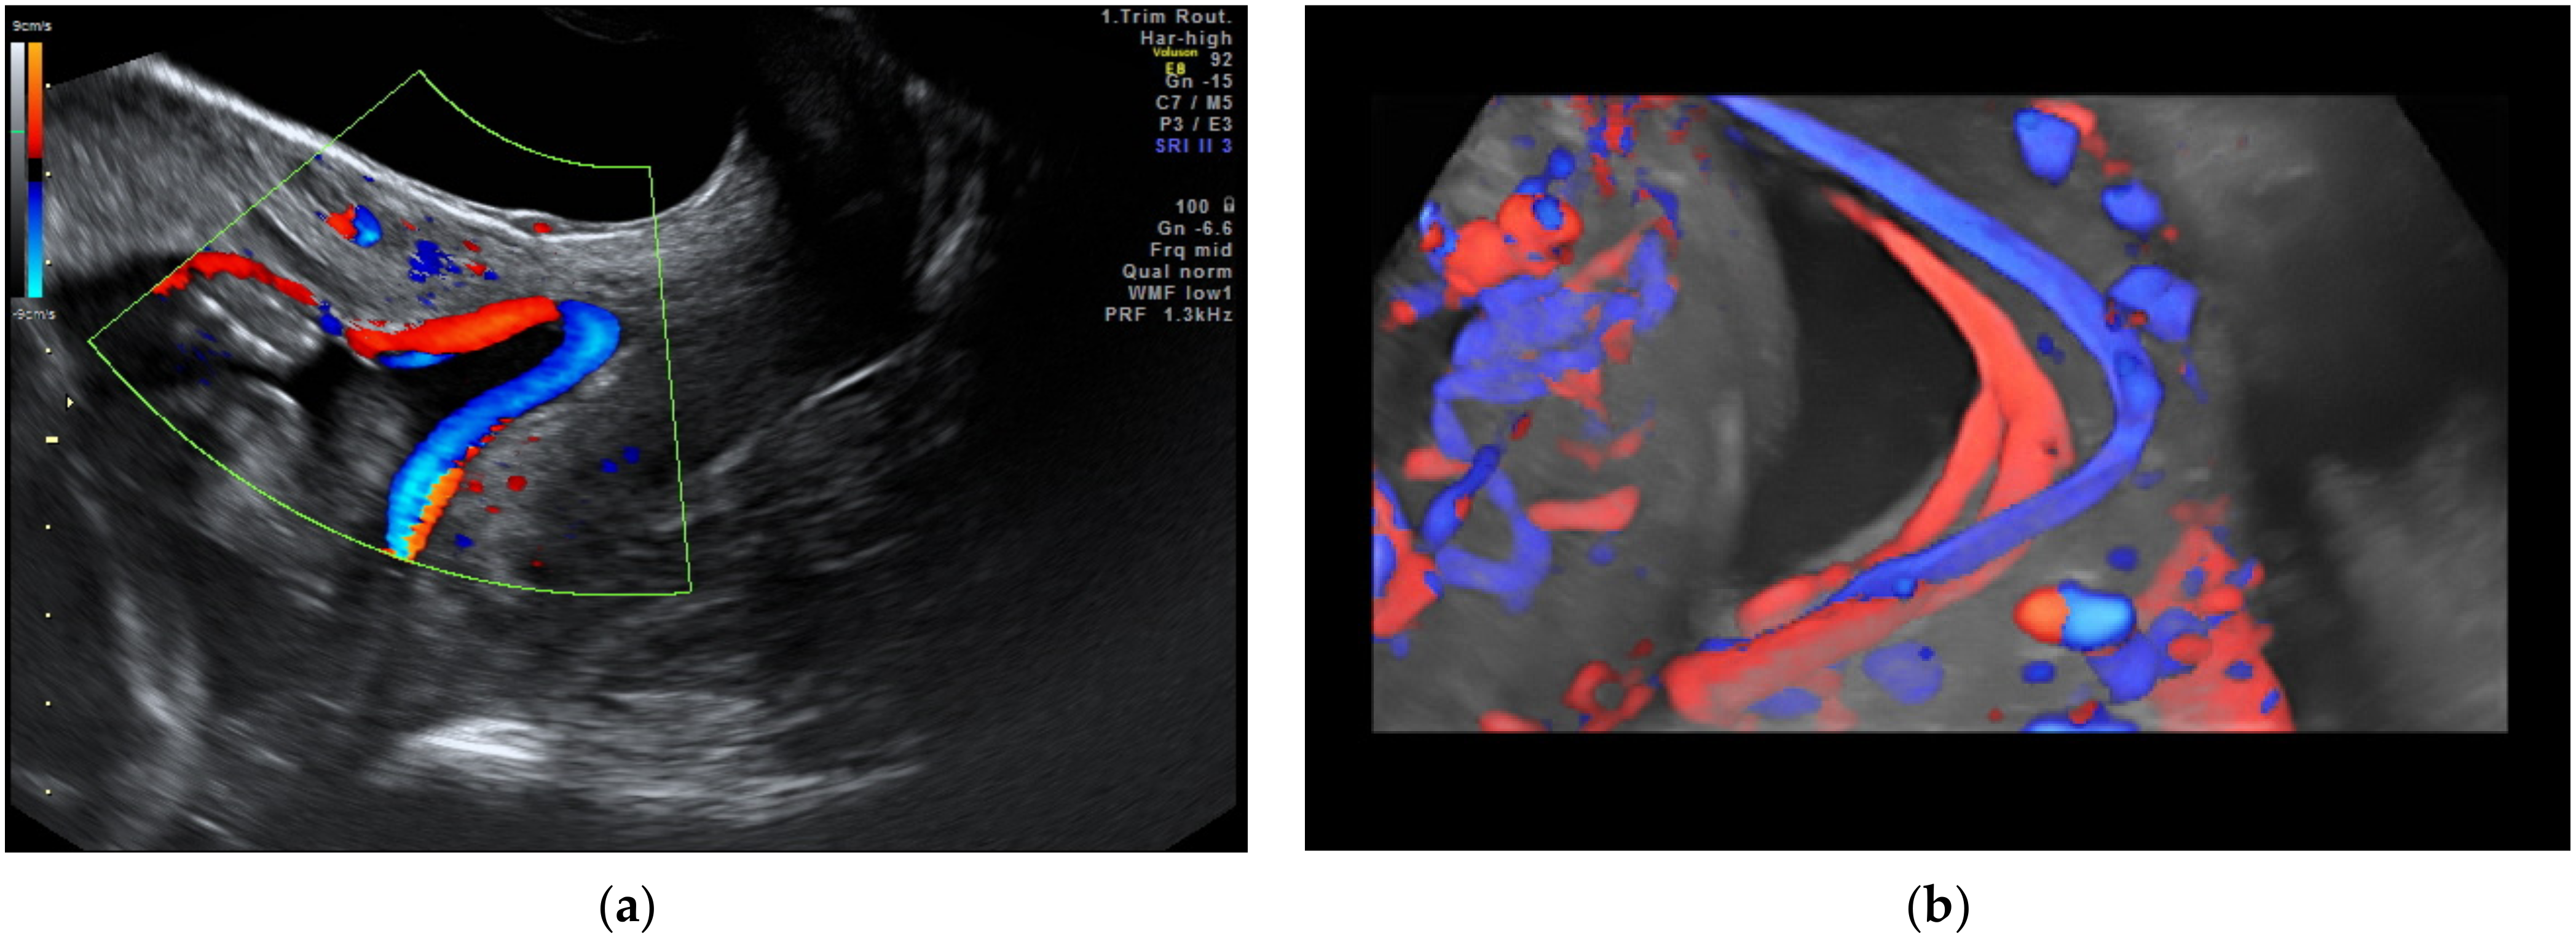

2.2. Vasa Praevia